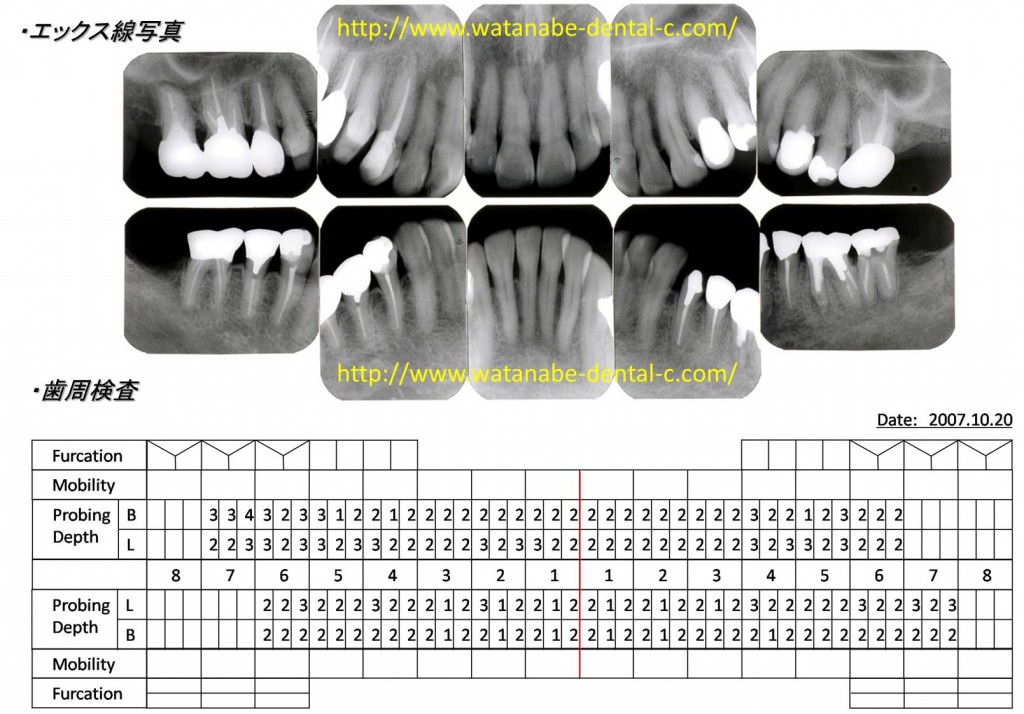

術後の口腔内写真・エックス線写真・歯周組織検査です。

付着歯肉を獲得した部位は歯肉が安定し、大臼歯部の歯周ポケットが改善しています。